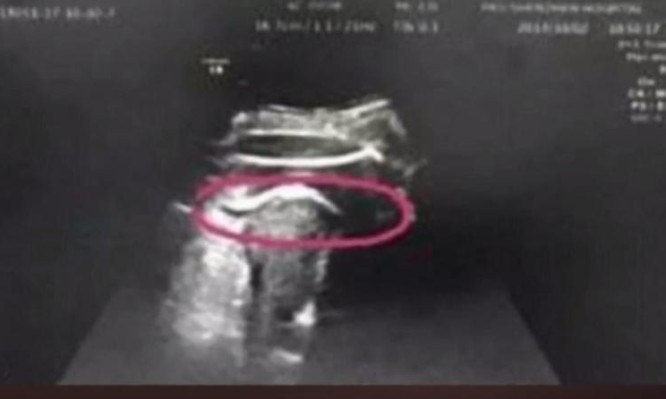

Ρήξη μήτρας από... δυνατή κλωτσιά του εμβρύου; Κι όμως συνέβη σε μία γυναίκα που ήταν έγκυος και η οποία τελικά γέννησε πρόωρα ένα υγιέστατο κοριτσάκι.

Ένα απίστευτο περιστατικό σημειώθηκε στην Κίνα. Πρωταγωνίστρια μια γυναίκα, έγκυος στην 35η εβδομάδα. Η οποία μεταφέρθηκε εσπευσμένα σε νοσοκομείο του Πεκίνου, αφού παραπονέθηκε για έντονους πόνους στην κοιλιακή της χώρα. Κάτι που έμελλε να αποδειχθεί πως ήταν… ρήξη μήτρας!